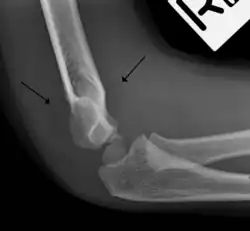

In addition to fracture, any process resulting in an elbow joint effusion may also demonstrate an abnormal fat pad sign. Increased intracapsular fluid is also seen in several conditions other than fracture and this produces the abnormal fat pad sign. (toxic synovitis, septic arthritis, Juvenile Rheumatoid Arthritis, osteomyelitis of the distal humeral physis and secondary septic joint). In these instances, history and clinical examination in addition laboratory results (WBC, ESR, CRP) will guide the provider in determining whether to treat the condition as an occult fracture or continue workup for other pathology.

The fat pad sign is invaluable in assessing for the presence of an intra-articular fracture of the elbow. An anterior fat pad is often normal. However a posterior fat pad seen on a lateral x-ray of the elbow is always abnormal. The patient will be unable to flex their elbow and requires orthopaedic input.[2]